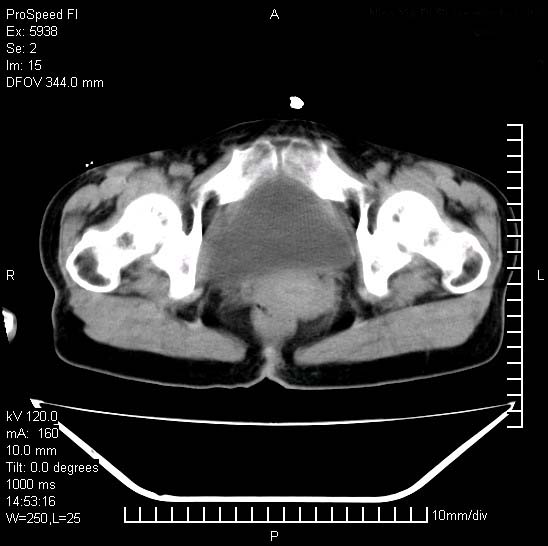

反复小腹疼痛,盆腔积液3年,无发热,曾抗痨一段时间。

右下腹肠管壁增厚,边缘有侵润改变及点状低密度影,内侧可见局限性肿块。考虑-----淋巴瘤或增生型肠结核----盆腔积液-----建议肠镜检查

考虑盆腔及右下腹感染性病变(结核可能)。

结核性腹膜炎伴积液。右侧髂骨骨窗看看,是否有骨质破坏。

提示结核性腹膜炎合并盆腔积液。建议查ppd或tb抗体。